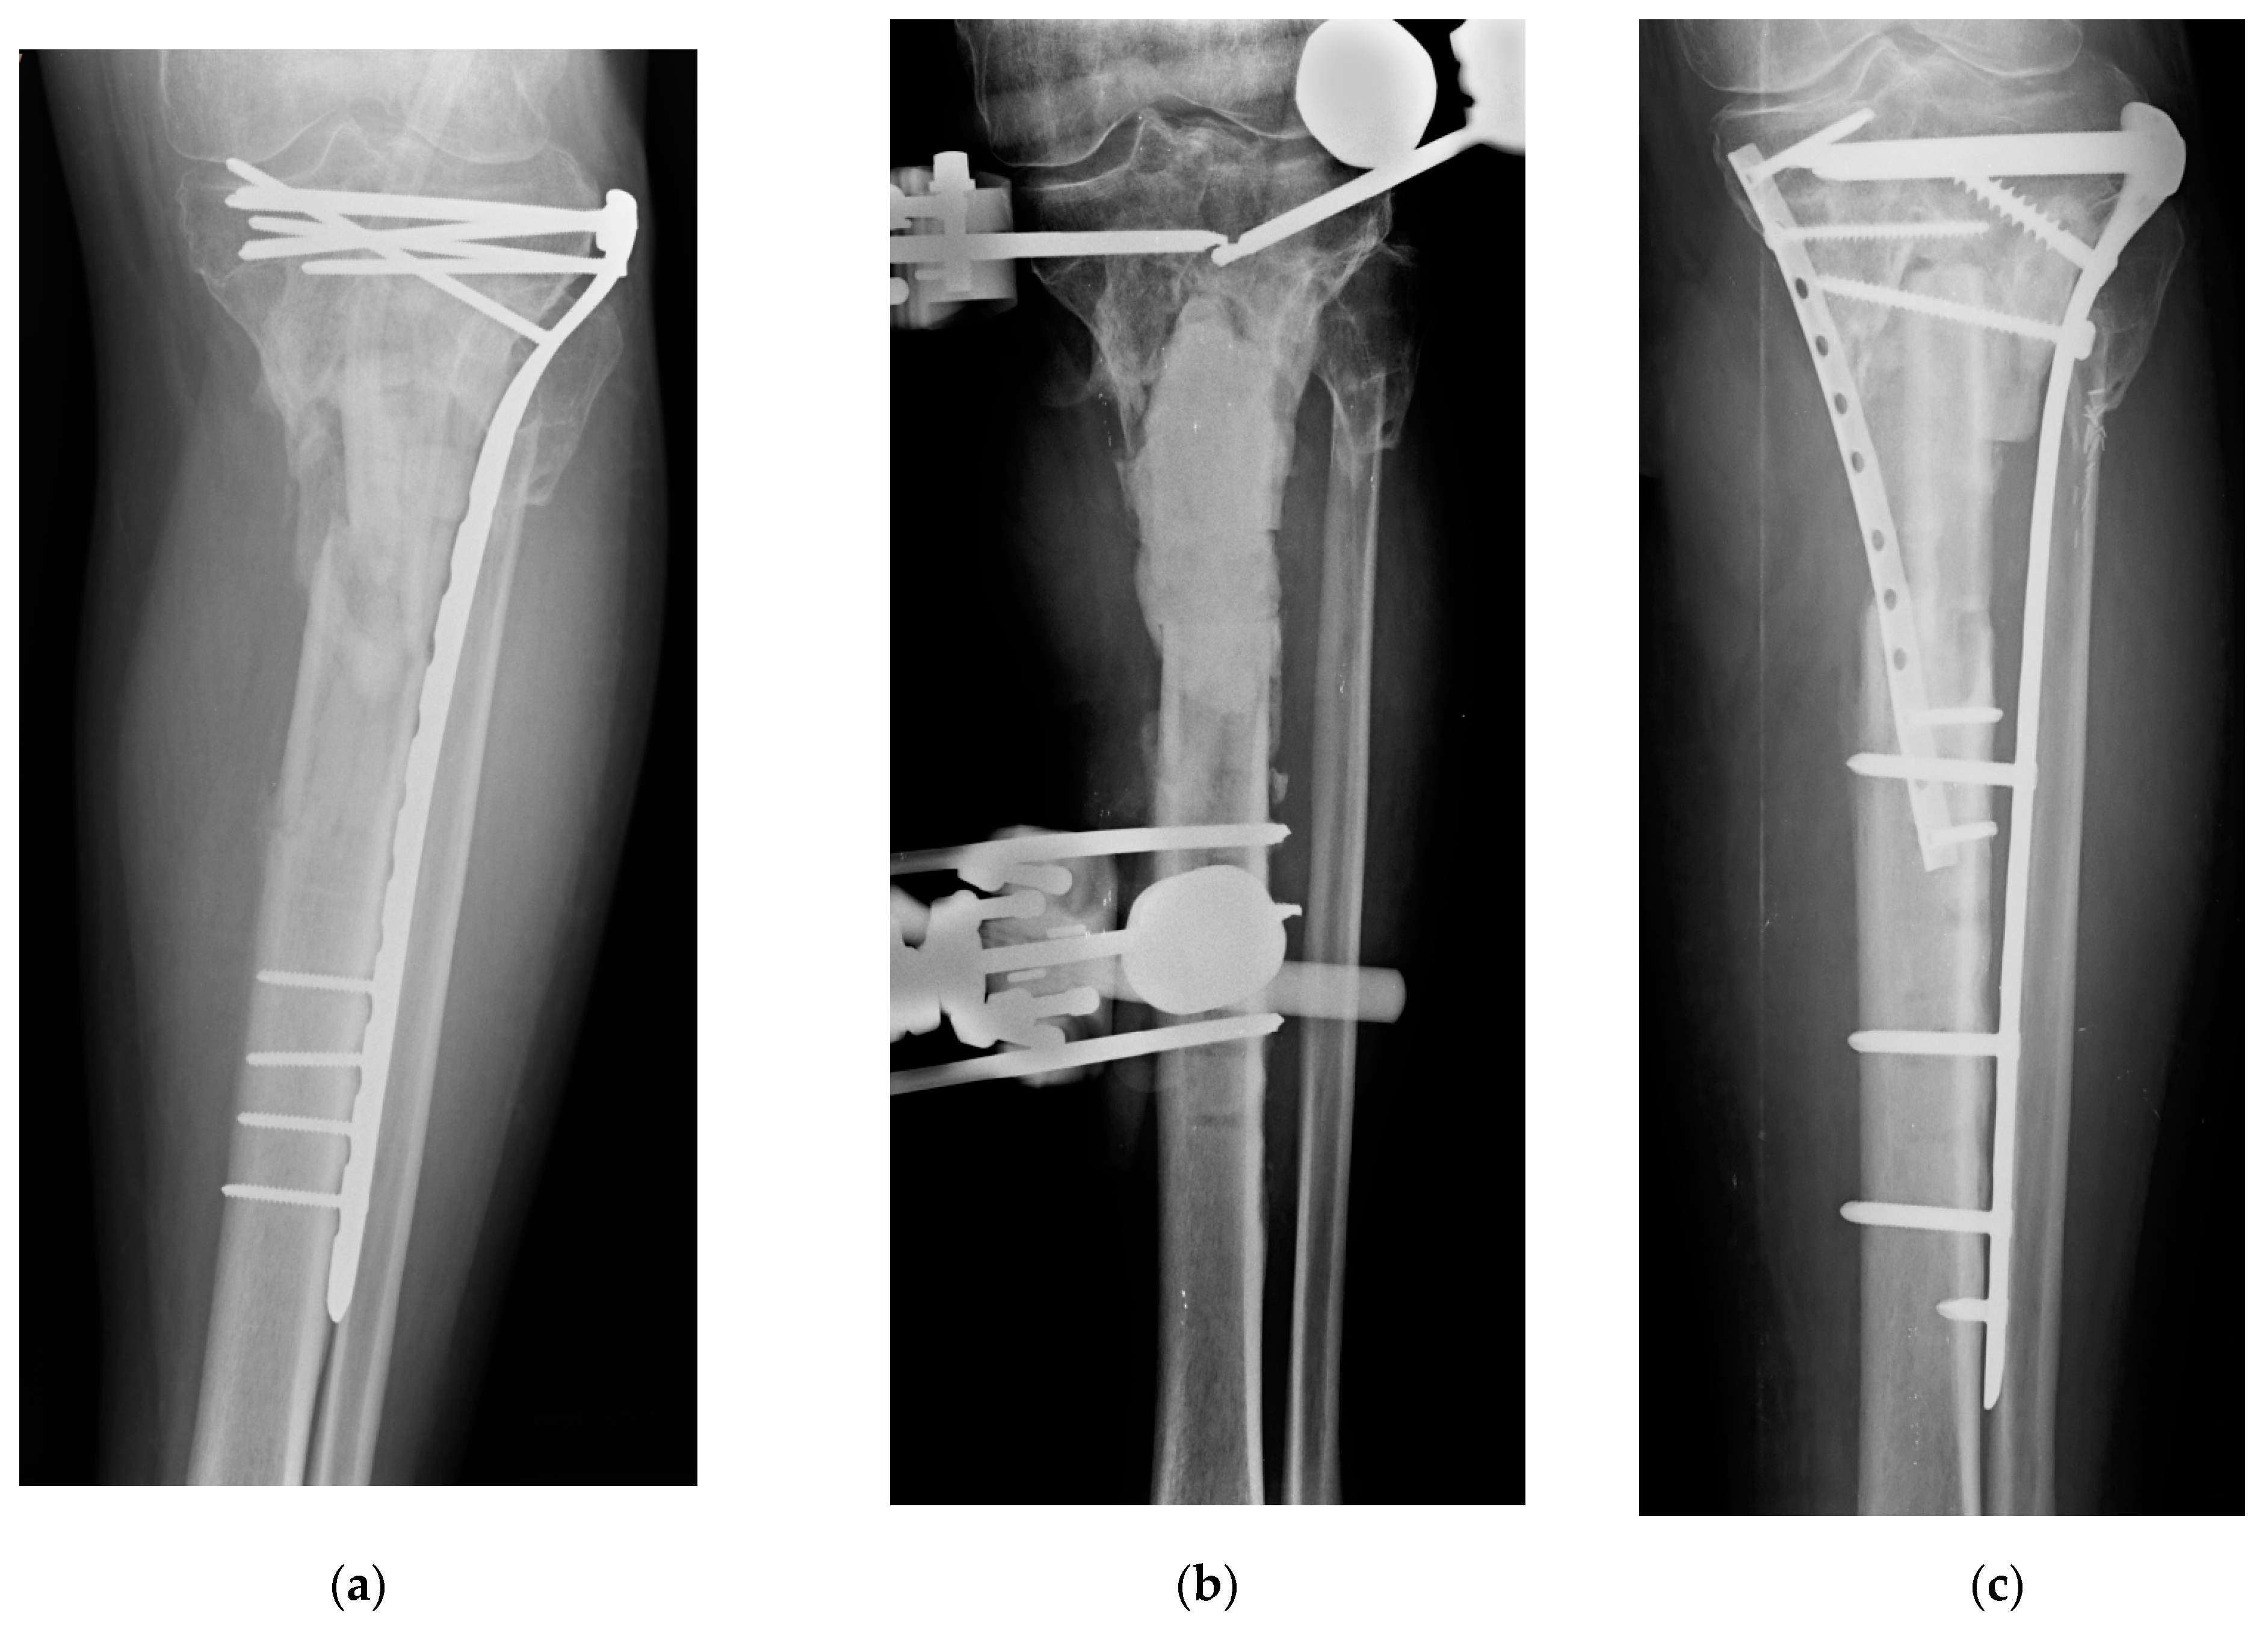

- Malizos, K.; Blauth, M.; Danita, A.; Capuano, N.; Mezzoprete, R.; Logoluso, N.; Drago, L.; Romanò, C.L. Fast-resorbable antibiotic-loaded hydrogel coating to reduce post-surgical infection after internal osteosynthesis: A multicenter randomized controlled trial. J. Orthop. Traumatol. 2017, in press. [Google Scholar] [CrossRef] [Green Version]

- De Meo, D.; Cannari, F.M.; Petriello, L.; Persiani, P.; Villani, C. Gentamicin-Coated Tibia Nail in Fractures and Nonunion to Reduce Fracture-Related Infections: A Systematic Review. Molecules 2020, 25, 5471. [Google Scholar] [CrossRef]

- Pinto, D.; Manjunatha, K.; Savur, A.D.; Ahmed, N.R.; Mallya, S.; Ramya, V. Comparative study of the efficacy of gentamicin-coated intramedullary interlocking nail versus regular intramedullary interlocking nail in Gustilo type I and II open tibia fractures. Chin. J. Traumatol. 2019, 22, 270–273. [Google Scholar] [CrossRef]

- Metsemakers, W.-J.; Reul, M.; Nijs, S. The use of gentamicin-coated nails in complex open tibia fracture and revision cases: A retrospective analysis of a single centre case series and review of the literature. Injury 2015, 46, 2433–2437. [Google Scholar] [CrossRef]

- Moghaddam, A.; Weis, J.; Haubruck, P.; Raven, T.F.; Addali, A.; Schmidmaier, G. Evaluation of the clinical use of the ETN PROtect® in non-union therapy. Injury 2019, 50, 32–39. [Google Scholar] [CrossRef]